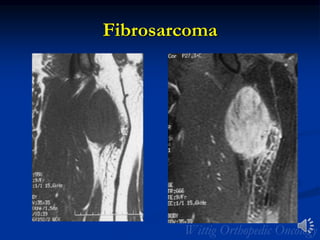

Fibrosarcoma

• Definition: Malignant tumor of fibroblasts that shows no

other evidence of differentiation. The spindle cells are

usually uniform and demonstrate minimal

pleomorphism.

• Rare: 5% of all soft tissue sarcomas

• 40 to 55 years of age; Infantile form <10 yrs of age

• Sites: Intramuscular; rarely in subcutaneous tissue

• Thigh, knee area, buttock

• Arm/shoulder girdle

• Trunk

• Forearms and legs

• Clinical: Painless mass

• Overall 5 yr. survival of 40%

• >60% metastatic rate

• Virtually indistinguishable from MFH on

imaging

Radiology

• MRI

• 2/3 of tumors are intramuscular

• Well defined heterogeneous mass

• Necrosis and hemorrhage are common especially in

higher grade tumors

• Viable areas enhance with contrast; Areas of

significant necrosis and hemorrhage do not enhance